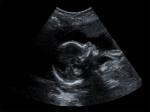

Уже давно установлено, что следствием длительного пребывания в сидячем положении является застой крови в малом тазу, ухудшение кровоснабжения органов, находящихся в брюшной полости, включая матку. А это может привести к гипоксии плода. Тем более что нередко беременные женщины проводят рабочий день, а это восемь часов, перед компьютером в офисе, представляющем собой многолюдное, душное и непроветриваемое помещение.